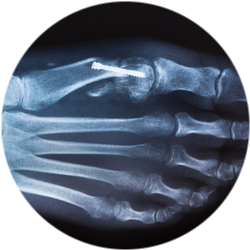

Этот вид оперативного вмешательства проводят из разрезов длиной от 3 до 6 сантиметров. Во время процедуры врач полноценно видит область операции, контролирует положение костных структур после их перемещения, оценивает расположение металлоконструкций, которыми фиксируются костные фрагменты. Традиционные реконструктивные операции отличаются длительным сроком реабилитации и применяются при запущенных случаях.

Врач рассекает 1 плюсневую кость (остеотомия), перемещает кости в нужное положение, проводит их фиксацию с помощью металлоконструкции.